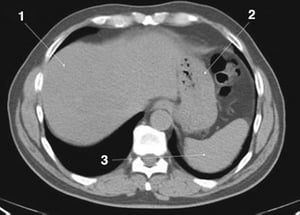

CT-Scan von Abdomen und Becken mit normaler Anatomie ohne Kontrastmittel (Folie 3)

1 = Leber; 2 = Magen; 3 = Milz.

© Springer Science+Business Media